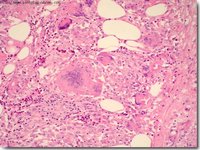

肌肉纖維瘤鏡下見腫瘤含有豐富的膠原纖維,病變無包膜,與周圍組織無界限,有時將周圍組織包括在病變中,核分裂罕見,毛細血管及脂肪細胞較少見。少數復發病例可出現纖維肉瘤的形態變化。